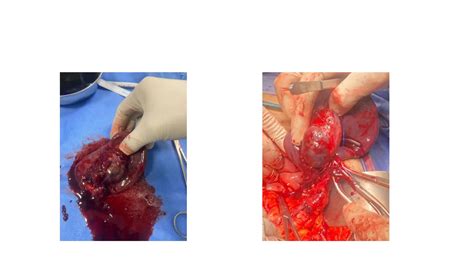

• Open Surgery: Traditional open surgery involves making an incision in the abdomen to access the splenic artery. The aneurysm is repaired or the artery is ligated (tied off) to prevent further dilation.